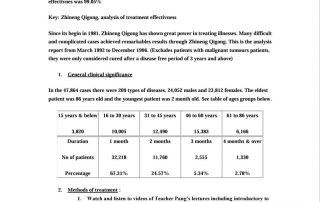

Casos de recuperación y mejora

Estudios

Desde Universe Healing recopilamos e investigamos documentación científica sobre el Qì Gong y las demás disciplinas que están relacionadas con la sabiduría oriental como la Medicina Tradicional China, el Tai Chi, Meditación, etc.

- Base de datos sobre publicaciones científicas – Nacional Library of Medicine.

- Publicaciones científicas sobre la medicina china en ingles. 407.272 resultados

- Meditación – 3.794 resultados

- Qi gong – 3.248 resultados

- Reiki – 3.685 resultados

- Tai Chi – 4.467 resultados

- Kung fu – 5.066 resultados